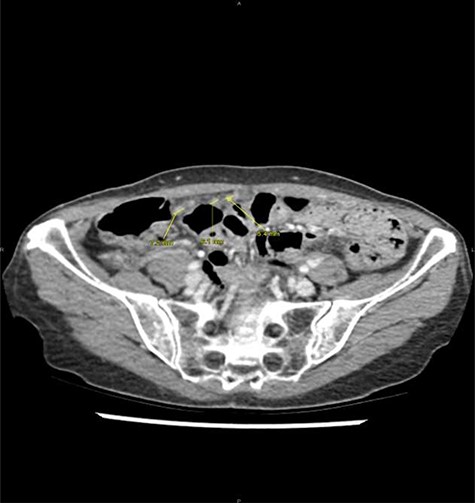

After refusing any anticancer treatment therapy, the patient died 1 year after appendicectomy. By retrospectively analysing imaging performed at the emergency department, we observe that the nodules of peritoneal carcinomatosis could be identifiable on CT images (Fig. 2).

Peritoneal noduli observed after retrospective analysis of abdominal computed tomodensitometry (yellow arrow).